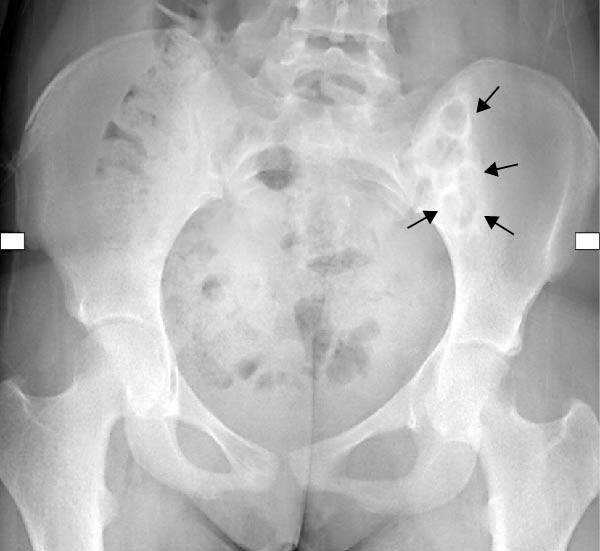

При дальнейшем обследовании у нее были обнаружены изменения костной ткани вследствие гиперпаратиреоза (рис. 3-4) и нефрокальциноз почек (по данным УЗИ).

Рисунок 4. Рентгенограмма таза в переднезадней проекции, на которой видно четко очерченное литическое поражение левой подвздошной кости со склеротическими границами (стрелки).